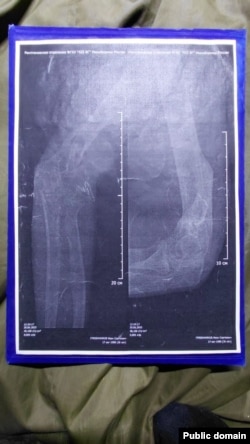

Паводле мэдычных дакумэнтаў Грабеньнікава, 30 чэрвеня 2025 году лекар-нэўроляг правёў агляд і паставіў дыягназ, пазначыўшы катэгорыю прыдатнасьці да вайсковай службы — «Д» (цалкам не прыдатны). Нэўроляг даў накіраваньне Грабеньнікаву ў Бранку (горад у Луганскай вобласьці Ўкраіны) для «лячэньня, праходжаньня вайскова-лекарскай камісіі і афіцыйнага вызначэньня катэгорыі прыдатнасьці». Аднак усе прызначэньні лекара камандаваньне праігнаравала — Грабеньнікава і іншых параненых, вернутых пасьля палону, гвалтам адправілі на фронт.

Здымкі зламанай рукі Івана Грабеньнікава

— Нам здавалася, што па вяртаньні з палону нас хаця б лячыць будуць. Куды там — нам нахабна памянялі катэгорыі на фальшывыя, мне, напрыклад, маю «Д» замянілі на «Б» (прыдатны да службы зь нязначнымі абмежаваньнямі), хоць у мяне правая рука як была ў некалькіх месцах перабітая — так і вісіць. У мяне дагэтуль куля ў целе — нават не апэравалі, — кажа Іван. — І нас такіх вельмі шмат — на мыліцах, у гіпсе. Ім проста п…й, вязуць на Данецкі кірунак калек.